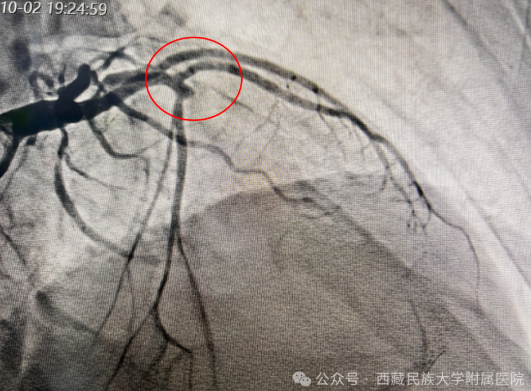

(图3:冠脉造影结果,前降支近端起闭塞)

手术在紧张而有序的氛围中展开。孙丽荣医师带领团队沉着冷静、操作娴熟,在数字减影血管造影(DSA)精准引导下,顺利将导管送至病变部位。随着闭塞血管被成功开通,心肌血流恢复灌注,患者上腹痛症状迅速缓解,生命体征逐步平稳。术后,当患者露出安心的笑容时,连续奋战的医护人员才稍稍松了一口气。这一刻,是医者仁心的最好见证,连日坚守岗位的医护人员也由衷感到欣慰。